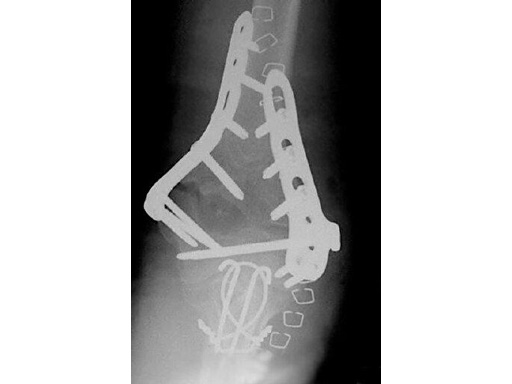

85-year-old woman, 13-C3, low supracondylar fracture treated with DHP.